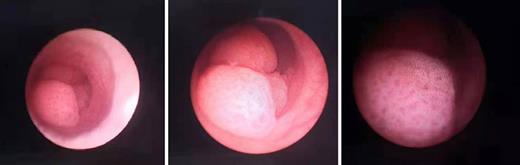

Another 3 months later, urethrocystoscopy was performed again. A cauliflower-like neoplasm was found in the right-top wall of the bladder, and three neoplasms were found in the calices. Four days later, TURBT and ureteroscopic retrograde tumor ablation were performed. Biopsies were also taken, and later they suggested that there were high-grade papillary urothelial carcinomas in the calices and chronic inflammation in the bladder. After the operation, tislelizumab (200 mg, ivgtt) and BCG (120 mg, bladder instillation) were applied regularly for target therapy and chemotherapy.